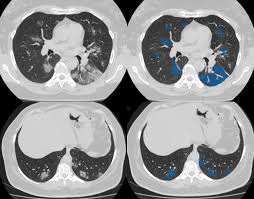

Entropy Free Full Text Classification Of Covid 19 Coronavirus Pneumonia And Healthy Lungs In Ct Scans Using Q Deformed Entropy And Deep Learning Features Html

Entropy Free Full Text Classification Of Covid 19 Coronavirus Pneumonia And Healthy Lungs In Ct Scans Using Q Deformed Entropy And Deep Learning Features Html from www.mdpi.com